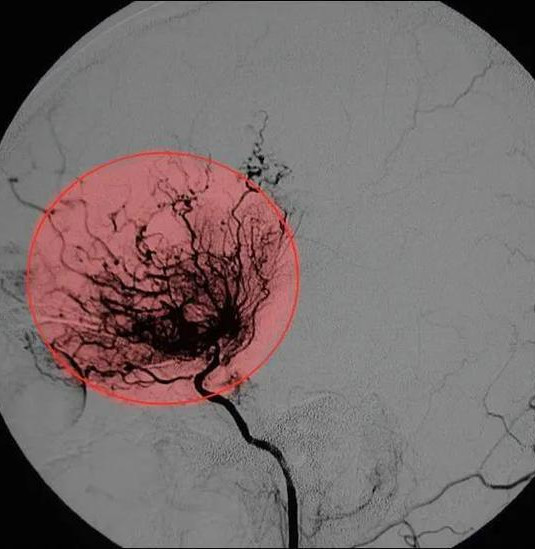

烟雾病血管造影图

烟雾病血管造影图,正常脑血管造影图

血管在脑血管造影图像上就像袅袅升起的炊烟,故被形象的称为"烟雾病"

术前造影显示,患者双侧颈内动脉末端闭塞,颅内烟雾状血管形成

脑血管病 ,因患者脑血管造影影像类似于烟雾而著名